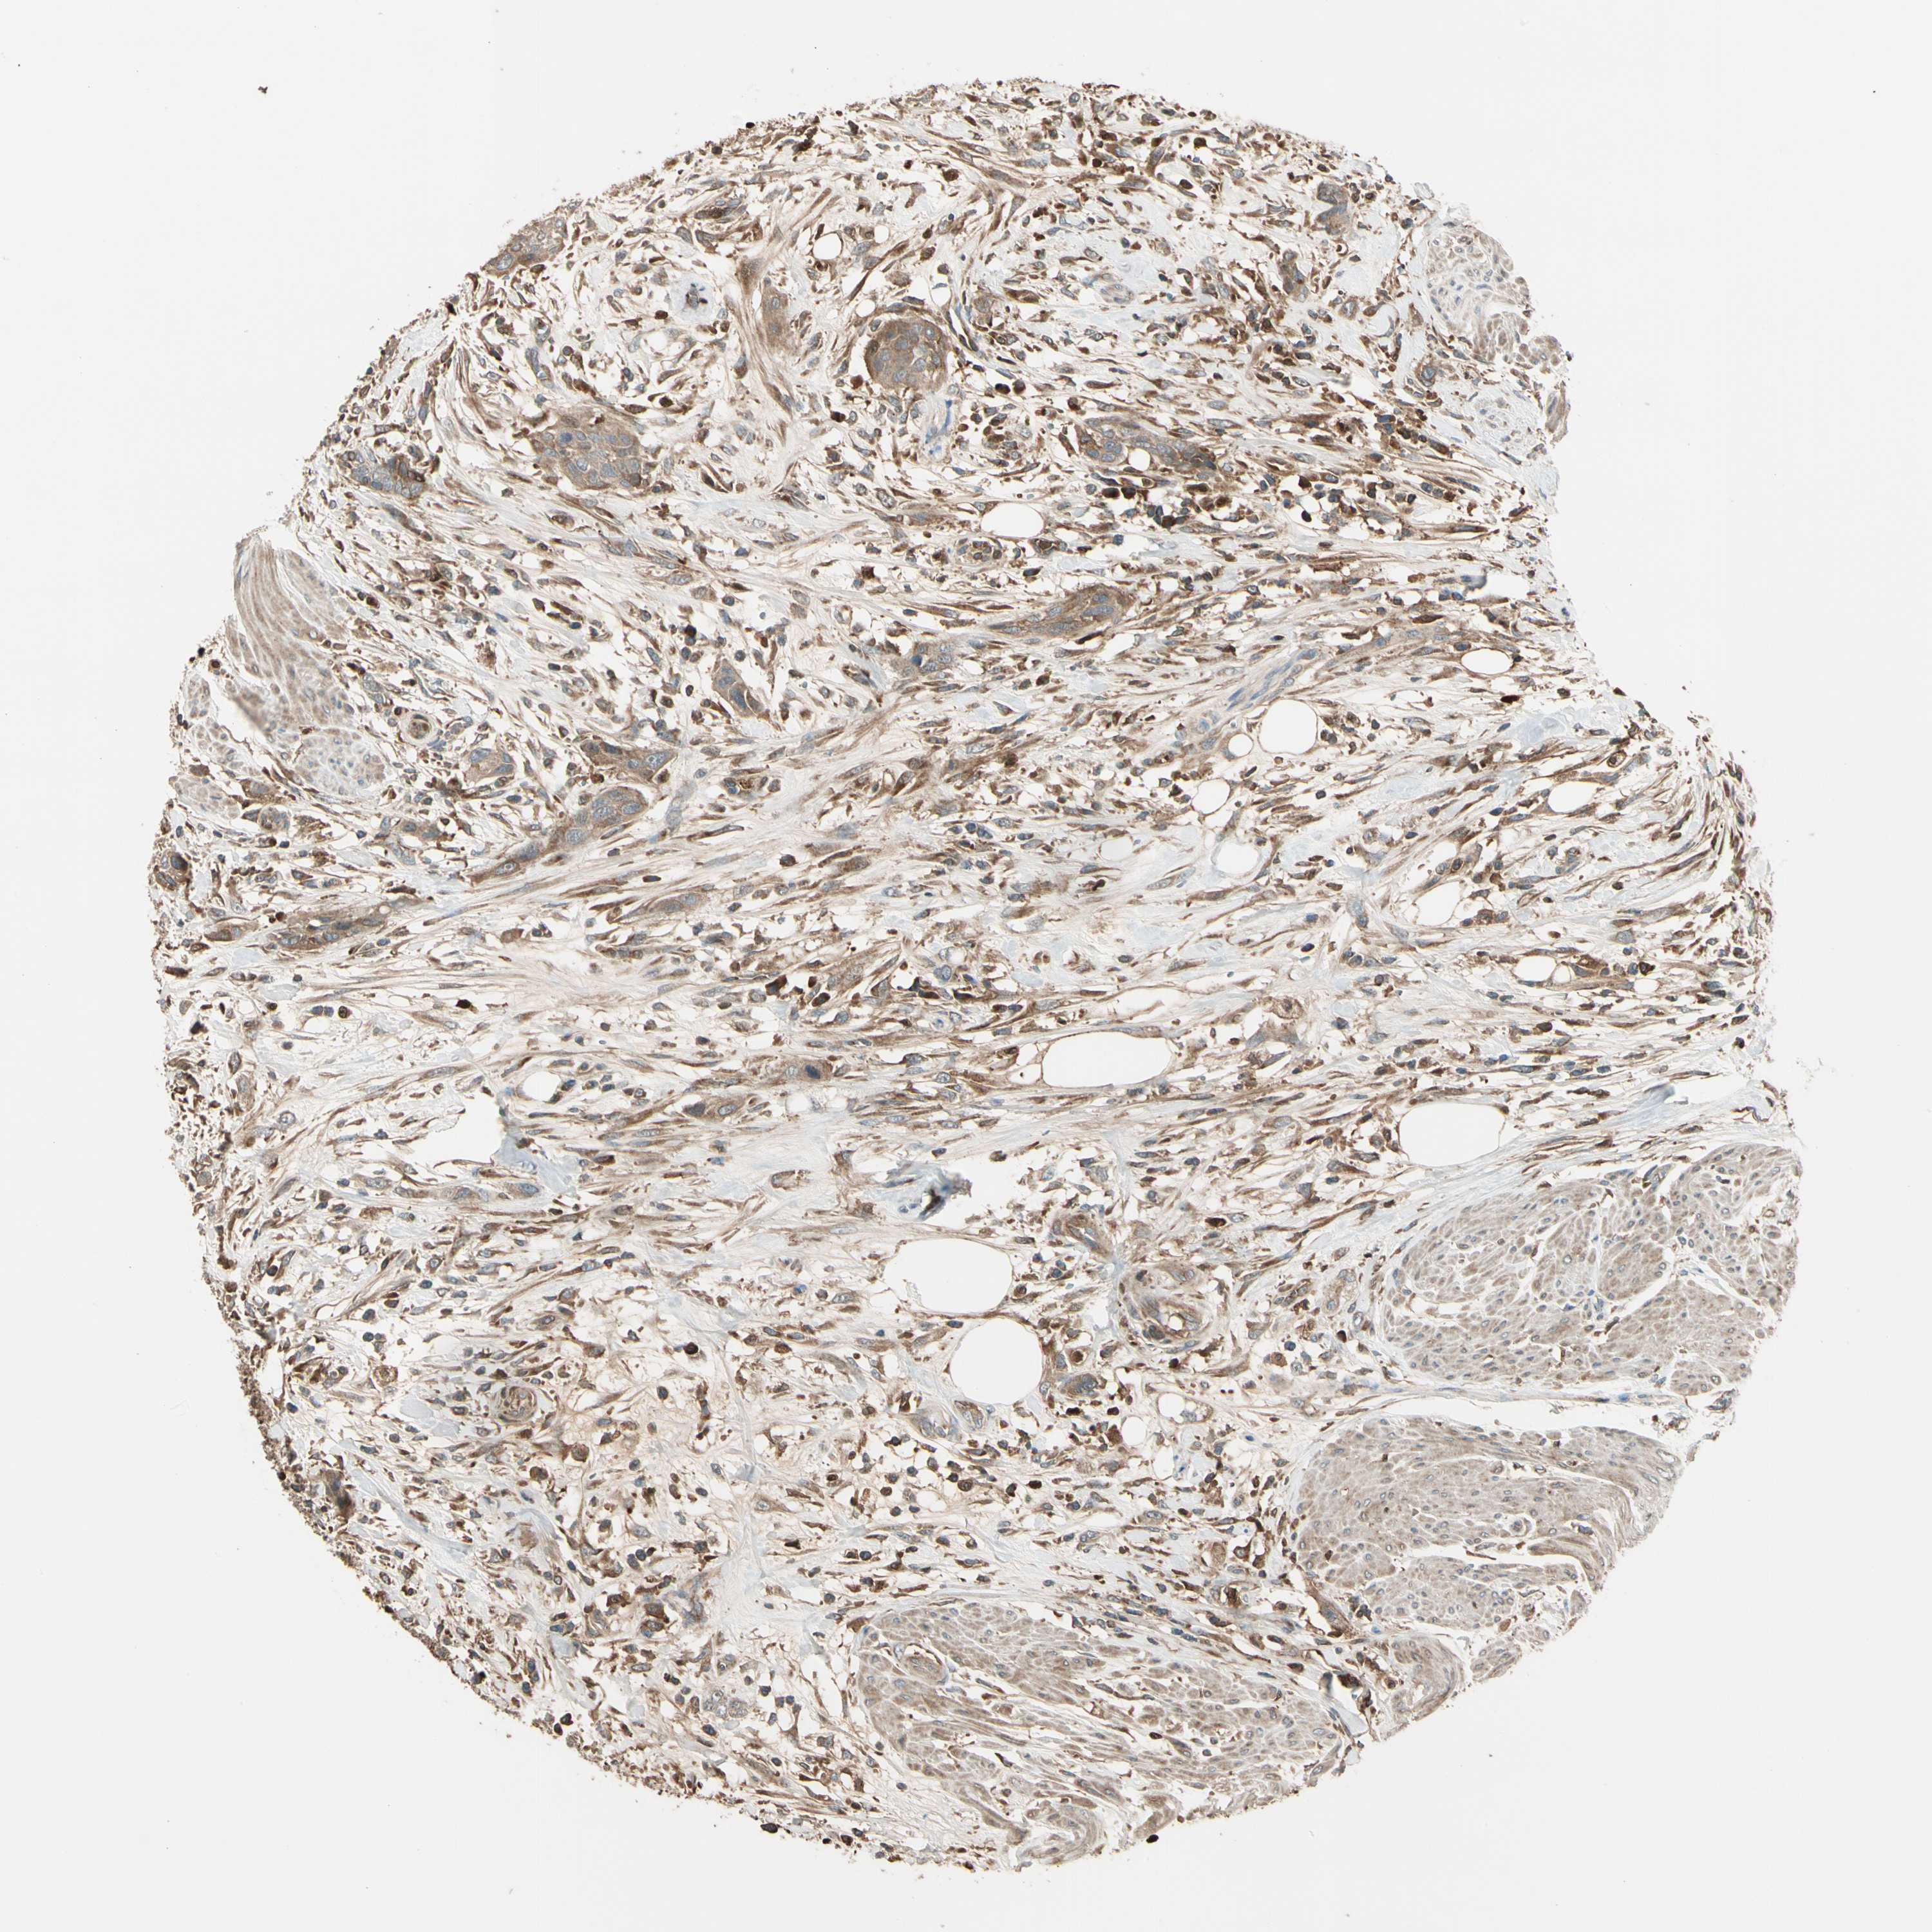

UROTHELIAL CANCER - Protein expressioni

A mouse-over function shows sample information and annotation data. Click on an image to view it in a full screen mode. Samples can be filtered based on level of antibody staining by selecting one or several of the following categories: high, medium, low and not detected. The assay and annotation is described here.

Note that samples used for immunohistochemistry by the Human Protein Atlas do not correspond to samples in the TCGA dataset.

Antibody stainingi

Antibody staining in the annotated cell types in the current human tissue is reported as not detected, low, medium, or high, based on conventional immunohistochemistry profiling in selected tissues. This score is based on the combination of the staining intensity and fraction of stained cells.

Each image is clickable and will lead to virtual microscopy that enables deeper exploration of all samples and also displays staining intensity scores, fraction scores and subcellular localization as well as patient and tissue information for each sample.

Antibody HPA007992

Staining

High

Medium

Low

Not detected

Intensity

Strong

Moderate

Weak

Negative

Quantity

>75%

75%-25%

<25%

None

Location

Nuclear

Cytoplasmic/membranous

Cytoplasmic/membranous,nuclear

Urothelial carcinoma, Low grade

Urothelial carcinoma, High grade